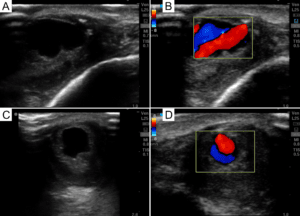

Lastly, with this November 2022 issue there emerged a theme in the case files and case reports: soft tissue examination using POCUS. Sheeka, et al. describe a diagnostic radiology case of a retained foreign body, but this is very important for POCUS users to learn from. Kaiyasah,et al. describe POCUS application in pilonidal sinus disease, a novel application for this common disease entity. Freilich et al. present a case of a soft tissue mass that was highly vascularized on POCUS examination, surprisingly found to be a post-traumatic AVM. McCreary, et al. describe the POCUS findings in a young patient with extraosseous Ewing’s sarcoma in the neck. Taken together, these cases highlight how usefully POCUS is in soft tissue examination beyond basic indications such as evaluating cellulitis for underlying abscess. While some of the above entities might be “rare”, POCUS users who scan soft tissue should be aware of these cases and use the discussion to expand their differential diagnosis of soft tissue findings accordingly.